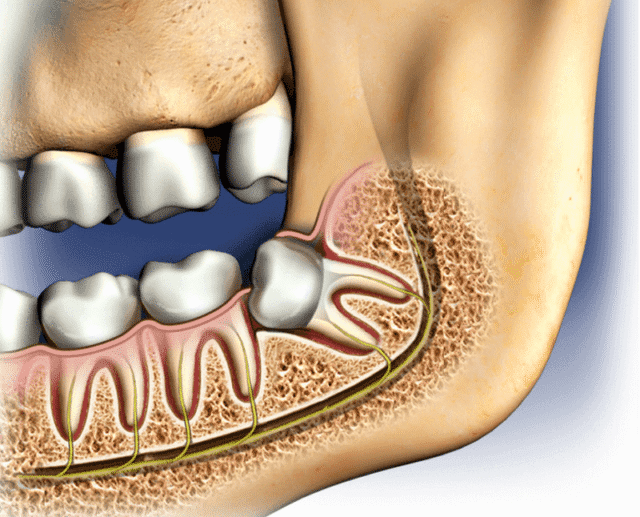

The Role of Expertise and Technology

Advanced surgical training, digital imaging, and modern protocols improve safety and success. These investments affect pricing but also protect patients from complications such as:

• Infection

• Nerve damage

• Long-term pain

• Repeat surgeries

Patients should view cost as an investment in safety.